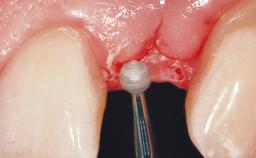

Ridge Preservation and Implant Placement for a Fixed Dental Prosthesis After a Car Accident

It is well known to clinicians that any removal of teeth will, over time, cause the dimensions of the alveolar ridge to be reduced by resorption of the bundle bone and by changes related to external modeling. This development is particularly evident in the crestal region with its thin buccal bone that consists of bundle bone almost entirely. The facial bone will rapidly resorb as blood supply from the periodontal ligament gets disrupted (Araújo and Lindhe 2005). There is no reason why traumatic tooth loss should not have the same consequences. It takes more than achieving implant osseointegration for a treatment outcome to be considered successful. No deficiency of bone or soft tissue is acceptable when an ideal esthetic outcome is the goal. Several articles (Sanz and coworkers 2011; Vignoletti and coworkers 2011) have reported on techniques of improving the alveolar ridge for implant treatment, notably focusing on protecting tissues from resorption.